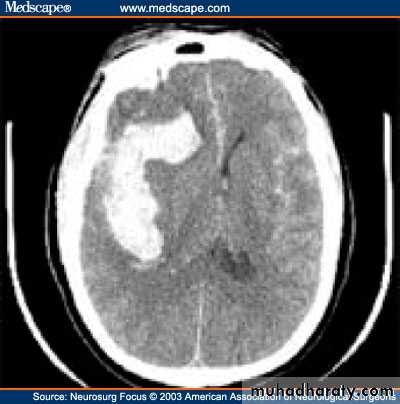

1) Acute subdural hematoma:

In the first 24 hours of the accident, the patient is unconscious in the whole course.

Diagnosis is by CT scan which will show a hyperdense mass.

Prognosis is usually bad and Treatment is by craniotomy, evacuate the hematoma, look for the bleeder and stop it thermally. Craniotomy is an obligation here because the injury is recent and the bleeder is still there, so if we do burr holes and evacuate the hematoma it may recollect again after a while.

Acute subdural hematoma